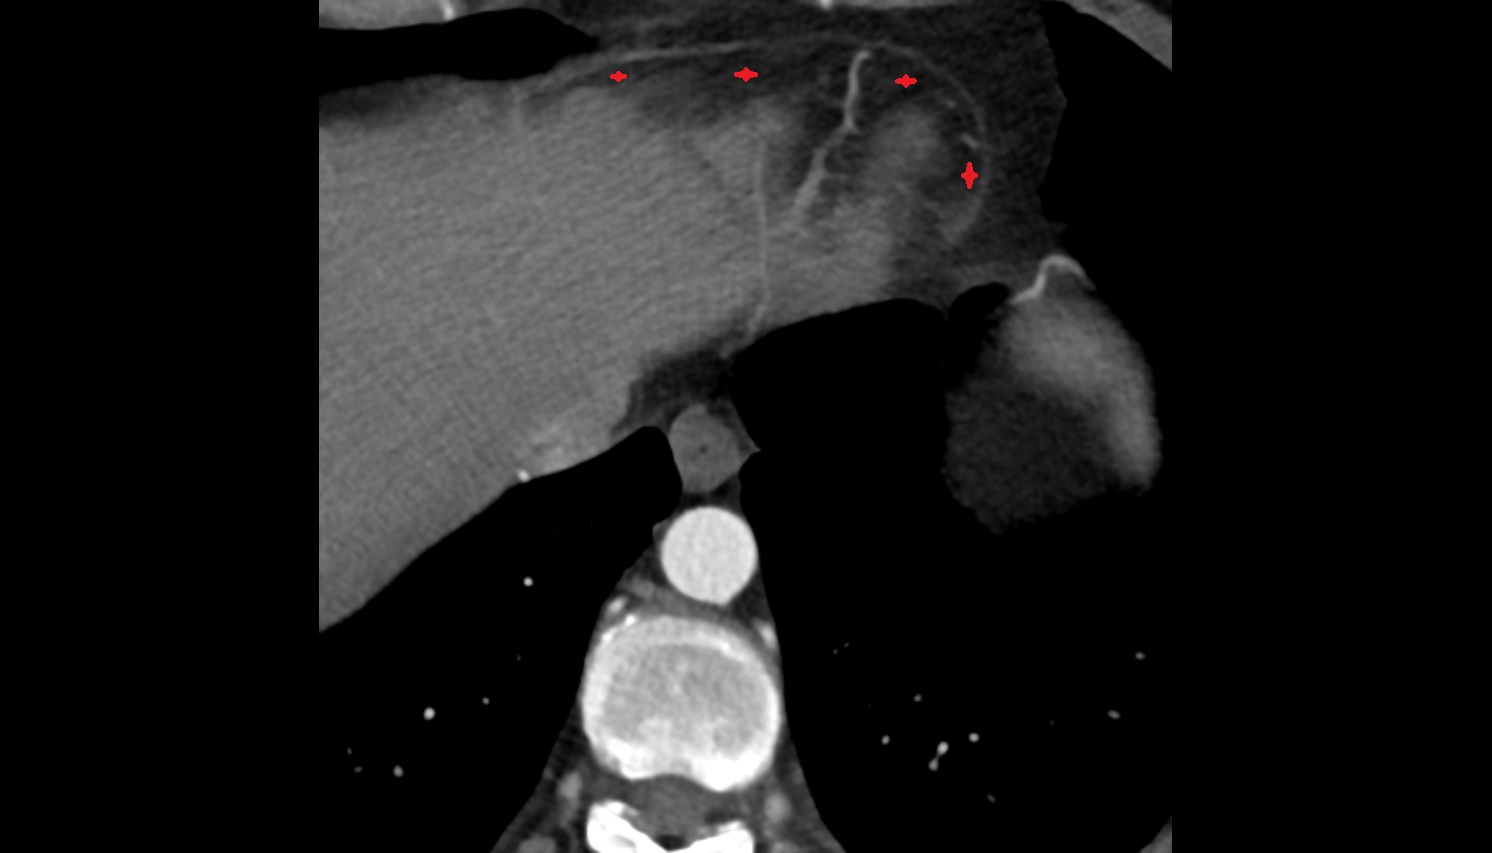

- Left anterior descending artery (LAD)

- Circumflex artery (LCx)

- Left main coronary artery (LMCA)

- Right coronary artery (RCA)